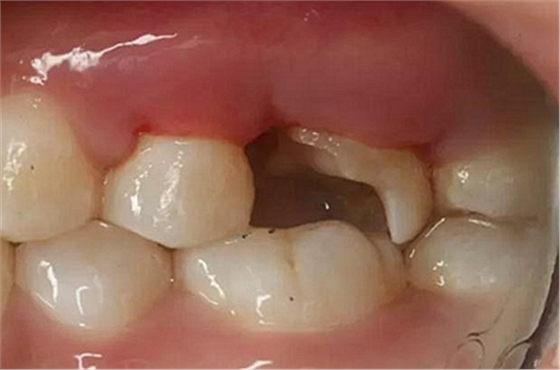

患者男性,35歲,B6銀汞充填后食物嵌塞,要求重新充填,口內(nèi)檢查見B6近中鄰頜面銀汞充填物,局部缺損,有繼發(fā)齲,去除原充填物及繼發(fā)齲,發(fā)現(xiàn)齲壞位于牙齦下方,給予冠延長手術(shù),同期嵌體預(yù)備,后一次性取模。(同樣設(shè)計為齦上邊緣)

硅橡膠取模后,灌注模型,科爾琥珀樹脂制作嵌體。